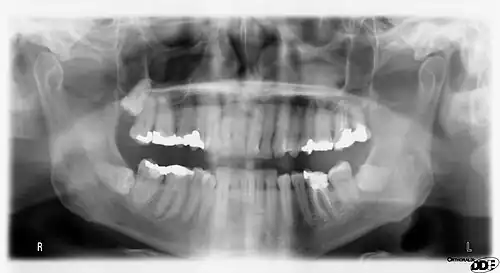

Panoramic radiograph

A panoramic radiograph is a panoramic scanning dental X-ray of the upper and lower jaw. It shows a two-dimensional view of a half-circle from ear to ear. Panoramic radiography is a form of focal plane tomography; thus, images of multiple planes are taken to make up the composite panoramic image, where the maxilla and mandible are in the focal trough and the structures that are superficial and deep to the trough are blurred.

Orthopantomograms (OPTs) are used by health care professionals to provide information on:

- Periodontal bone loss and periapical involvement.

- Finding the source of dental pain, and when carrying out tooth-by-tooth diagnosis.